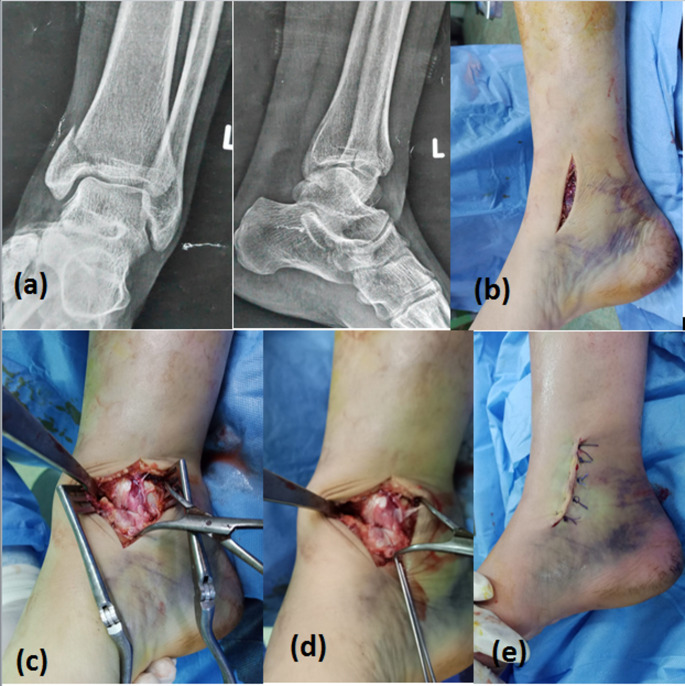

Introduction: Isolated medial malleolar (MM) fractures are infrequent injuries. Studies focused on their treatment are scarce. The aim of this study was to compare functional and radiographic outcomes of two surgical techniques for treatment of displaced isolated MM fractures in adults: closed reduction and percutaneous fixation (CRPF), and open reduction and internal fixation (ORIF) by using same implant; two partially-threaded cannulated cancellous screws.

Materials and methods: A prospective randomized controlled clinical trial (RCT) was conducted on 50 patients with isolated displaced MM fractures, treated with CRPF (group A) or ORIF (group B), at orthopaedics department of university hospital, from April 2021 to April 2023. Fractures were classified by Herscovici classification. The primary outcomes were incidence of complications and time to union based on radiographic assessment by plain radiographs of ankle. The secondary outcomes were functional assessment by Foot and Ankle Ability Measure (FAAM) for activities of daily living (ADLs) and sports, American Orthopaedic Foot and Ankle Society (AOFAS) score, and VAS.